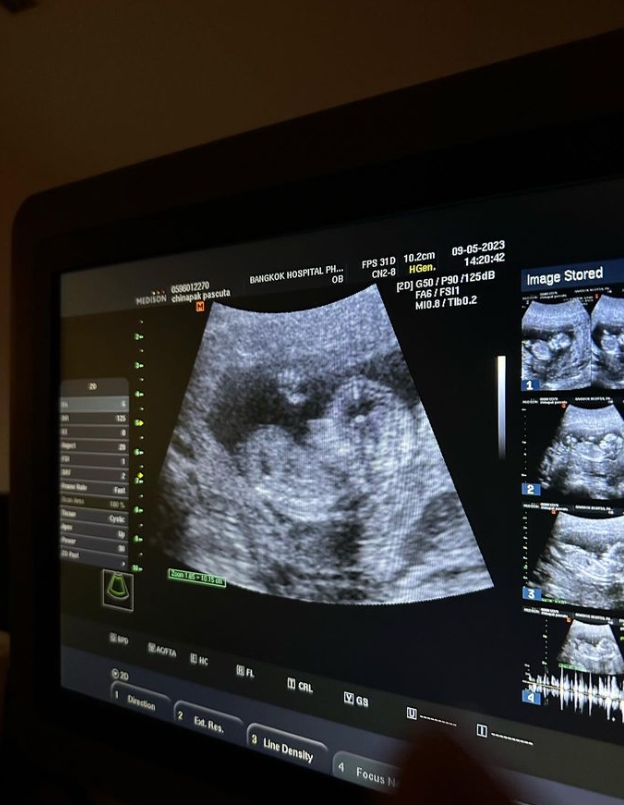

โดยว่าที่คุณป้า ได้โพสต์ภาพของน้องสาวพร้อมกับภาพอัลตราซาวด์ของหลาน พร้อมระบุแคปชั่นว่า

“I’m ready to be Auntie!🥹 หลาน Auntieแก้มมาแล้ว